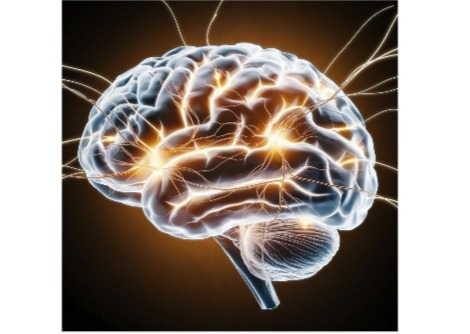

مكّنت تقنية "التجميد والتزحلق" العلماء من رصد إعادة تدوير المشابك العصبية فائقة السرعة في أنسجة دماغ الفئران والبشر، مُسلّطةً الضوء على الآليات الجزيئية المحفوظة.

أفاد باحثون في كلية الطب بجامعة جونز هوبكنز أنهم استخدموا تقنية "التجميد والتزحلق" لمراقبة تواصل خلايا الدماغ في أنسجة حية حقيقية مأخوذة من كل من الفئران والبشر. وقد مكّنتهم هذه التقنية من التقاط تفاعلات يصعب عادةً رؤيتها.

بعد ذلك، حفّز العلماء الخلايا العصبية في أنسجة دماغ الفأر باستخدام أسلوب التزجيج والتجميد، ولاحظوا أماكن اندماج الحويصلات المشبكية مع أغشية خلايا الدماغ، ثم إطلاق مواد كيميائية تُسمى النواقل العصبية، والتي تصل إلى خلايا الدماغ الأخرى. ثم لاحظوا كيف تُعيد خلايا دماغ الفأر تدوير الحويصلات المشبكية بعد استخدامها في التواصل العصبي، وهي عملية تُعرف باسم الالتقام الخلوي، والتي تسمح للخلايا العصبية بامتصاص المواد.